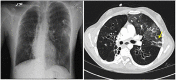

Non-tuberculous mycobacteria (NTM) are ubiquitous environmental organisms that may cause opportunistic infections in susceptible hosts. Lung infections in immunocompetent persons with structural lung disease are most common, while disseminated disease occurs primarily in immunocompromised individuals. Human disease caused by certain species, such as Mycobacterium avium complex, Mycobacterium abscessus, and Mycobacterium kansasii, is increasing in incidence and varies by geographic distribution. The spectrum of NTM disease varies widely in presentation and clinical outcome, but certain patterns can be organized into clinical phenotypes. Treatment options are limited, lengthy, and often toxic. The purpose of this case-based review is to provide non-clinician scientists with a better understanding of human NTM disease with an aim to stimulate more research and development.